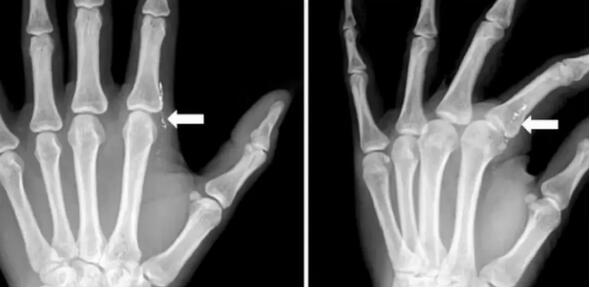

左食指第二掌指关节桡侧疼痛

▼

图片来源:J Hand Surg Asian Pac Vol. 2017 Dec;22(4):519-522.

X 片可见皮下线状高密度影